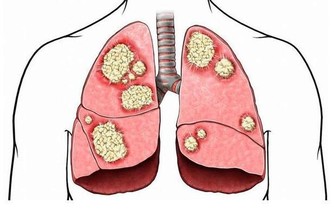

今日聽廣播,主持人說A型流感肆虐,馬偕醫院已有兩個病房染病,甚至包含醫護人員也中標。衛福部疾管署統計,春節期間因為流感併發重症已經有65例,9人死亡。我自己在門診量也是大增,真的不少民眾得A/B型流感從急診回診或新診斷,看來真的因為春節的返鄉潮,加速了流感的散播速度。

photos 流感和感冒,哪裡不一樣?